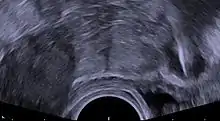

| Transvaginal ultrasonography showing a foreign body granuloma at right as a hypoechoic (dark) area around a perforated intrauterine device. The uterus is at left. | |